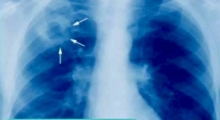

ежегодную флюорографию для подростков и взрослых;